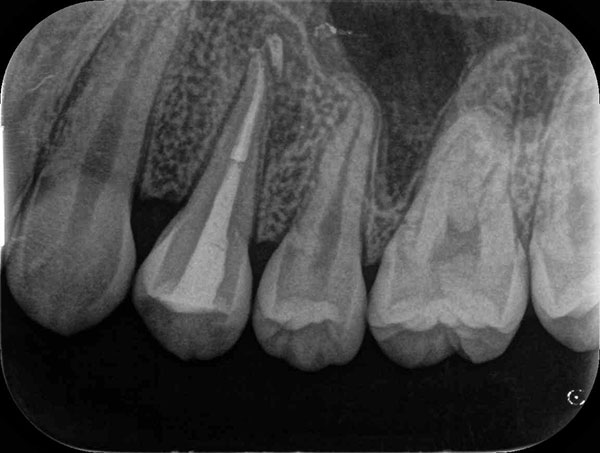

術前

術後

症例について

主訴:

歯茎にニキビみたいなのが出来た、歯ブラシを当てると違和感がある

治療内容:

根管治療で改善しない場合に、歯の根の先を外科的に取り除く治療です。

治療期間:90分1回

費用:165,000円(税込)

治療に関わるリスクまたは副作用:

術後に腫れや痛みが生じることがある